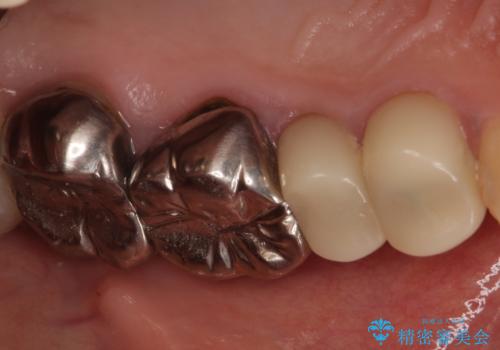

- 笑ったときに見てしまう上顎奥歯の銀歯を気にして来院された患者様です。

折角セラミッククラウンを装着するので、根管治療を行った後に補綴治療を行うこととしました。

他にも目立つ銀歯がありましたが、最も気にしている2本を優先して行うこととしました。

結婚式前にはクリーニングやホワイトニングを行い、その後他の歯を治療していく予定です。